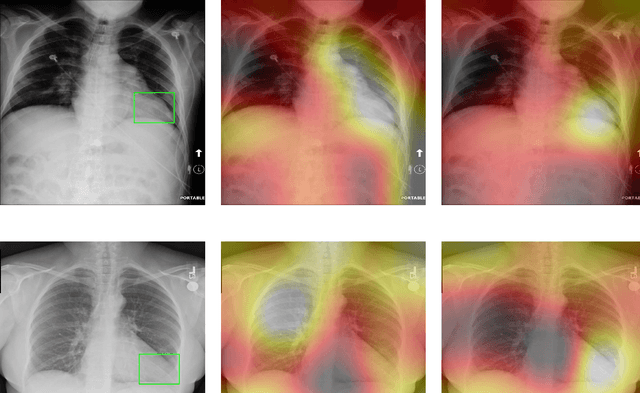

Abstract:Deep Learning has thrived on the emergence of biomedical big data. However, medical datasets acquired at different institutions have inherent bias caused by various confounding factors such as operation policies, machine protocols, treatment preference and etc. As the result, models trained on one dataset, regardless of volume, cannot be confidently utilized for the others. In this study, we investigated model robustness to dataset bias using three large-scale Chest X-ray datasets: first, we assessed the dataset bias using vanilla training baseline; second, we proposed a novel multi-source domain generalization model by (a) designing a new bias-regularized loss function; and (b) synthesizing new data for domain augmentation. We showed that our model significantly outperformed the baseline and other approaches on data from unseen domain in terms of accuracy and various bias measures, without retraining or finetuning. Our method is generally applicable to other biomedical data, providing new algorithms for training models robust to bias for big data analysis and applications. Demo training code is publicly available.